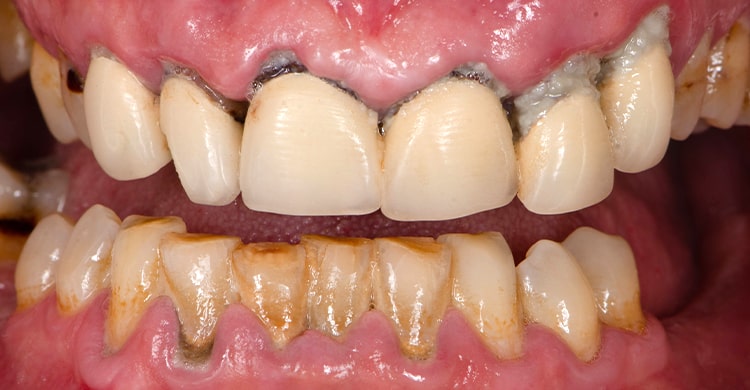

当院には、オールオン4治療で失敗してしまった患者さんが多数相談に来られます。そのほとんどが、他医院の格安なオールオン4治療を受けた方です。

インプラントのトラブルでご来院された患者様の症例写真。インプラントを除去せざるを得ませんでした。

オールオン4で埋入したインプラント体の周囲の組織についても、感染による炎症の恐れがあります。特に、上下ともオールオンフォーのケースよりも、ご自身の歯が残っているケースでは歯周病のコントロールができなければ、インプラントが脱落してしまうリスクもあります。

ご自身の歯を残して上下どちらかだけオールオン4にするようなケースについて、アバンダンスデンタル名古屋では術前治療として、徹底的に歯周病のコントロールを行います。